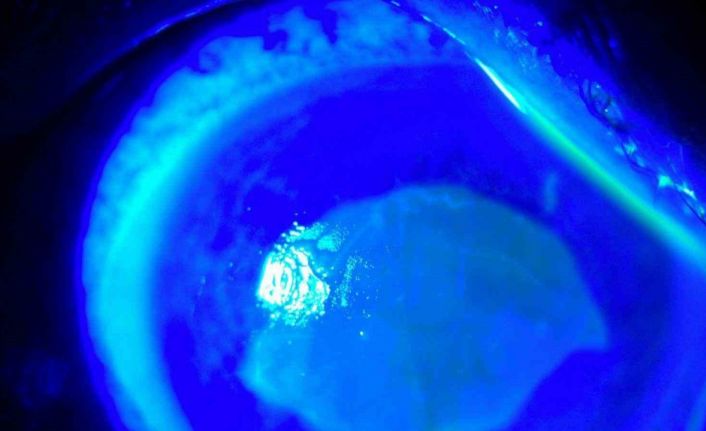

Kocaeli’nde yaşayan 52 yaşında kadın, iddiaya göre uzağı görememesi sebebiyle kullandığı gözlükten kurtulmak için yaklaşık 7 ay önce kırlangıç otunun suyunu gözlerine damlattı ve bir anda göremez hale geldi. Önce gözlerinde yanma, batma hisseden ve sonrasında açamaz hale gelen kadın hemen hastaneye koştu. O dönem Kocaeli’nde çalışan Göz Hastalıkları Uzmanı Doç. Dr. Ömer Faruk Yılmaz ve ekibi hastaya müdahale ederken korneanın en dış katmanı olarak ifade edilen kornea epitelinin zarar gördüğü belirlendi. Göze yabancı cisim, kimyasal madde kaçması ya da enfeksiyon durumlarında gözü temizlemek amacıyla uygulanan göz yıkama tedavisi gerçekleştirildi. Yaklaşık 2 haftalık tedavinin ardından hasta sağlığına kavuştu. Doç. Dr. Yılmaz, hastasının yaşadığı süreç ve tedavisine ilişkin bilgi verdi. Yılmaz, hekim önerisi olmadan herhangi bir ürün kullanılmaması gerektiğine dikkat çekerek önemli uyarılarda bulundu. Öte yandan hastanın göz bebeğinin beyazlığı ve göz akının ise kızardığı hali fotoğraf karesine yansıdı.

"Kırlangıç otu kullandı, hastamız göremez hale geldi eğer tedavi edilmeseydi sonucun ne olacağını bilemiyoruz fakat tedavi sonucunda hastamız iyileşti. Gözlerinin fotoğrafını çektirdim, kırlangıç otunun geçişini gösterdik. Tedavi edilmediği zaman göz içinde belki de körlüğe ulaşabilecek şekilde istenmeyen yan etkilere yol açabilir. Yüzlerce farklı ot olabilir, yanlışlıkla faydalı bir ot damlatacağız diye zararlı bir otu damlatabiliriz. Göze direkt damlatılması steril değildir, göze zarar verebilir, enfeksiyon oluşturabilir. Faydalı bile olsa Sağlık Bakanlığı ruhsat vermeden, ilaç formatına dönüştürmeden, uygun dozajlar ayarlanmadan ve göz hekiminin önerisi olmadan göze herhangi bir bitkisel ilaç damlatılmasını önermiyoruz."